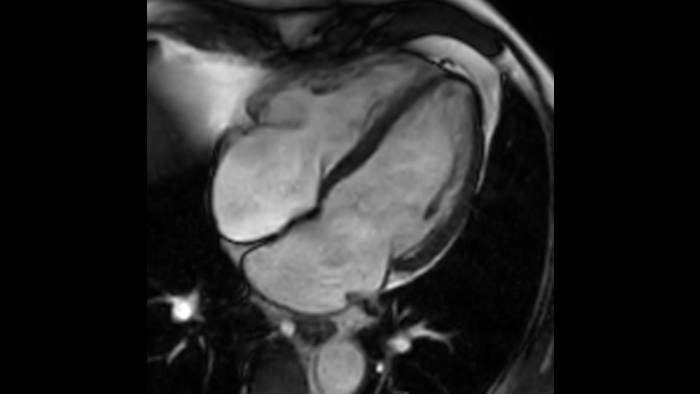

SmartSpeed SmartSpeed AI enables to decrease the scan time up to 65% with equal or better image quality

Diagnostic confidence Expand your imaging capabilities in all clinical areas. See how your peers are benefiting.

Speed & Comfort Provide up to 40% reduction in breath holds, with virtually equal image quality4.